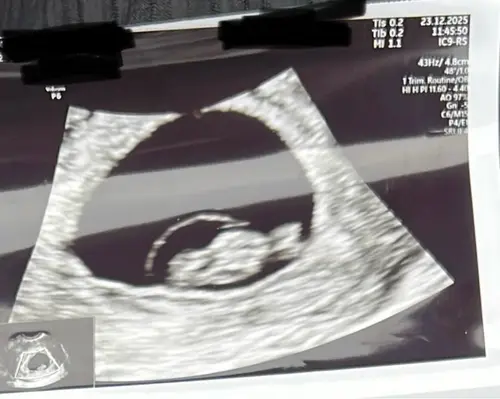

Nu 9+1, nog steeds alles helemaal in orde met allebei 😍🙏🏼🙏🏼

Begin er iets meer vertrouwen in te krijgen 🤞🏼♥️